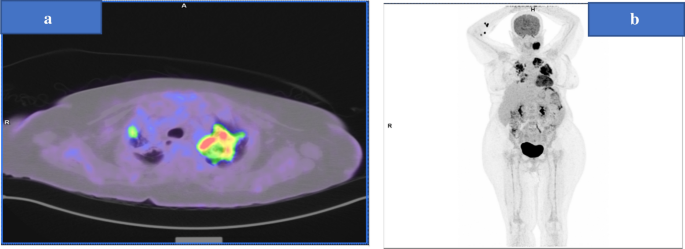

On 29th July 2019, she presented with a 1-week history of productive cough, high-grade fever, tachycardia, and low oxygen saturation (Temp: 39.2, HR: 130, SPO2: 91% on room air). Chest X-ray revealed a significant opacity in the left mid and lower lung zones (Fig. 5).

Chest XR showing large opacity noticed in the left mid and lower lung zones and Right upper zonal nodular and reticular shadowing